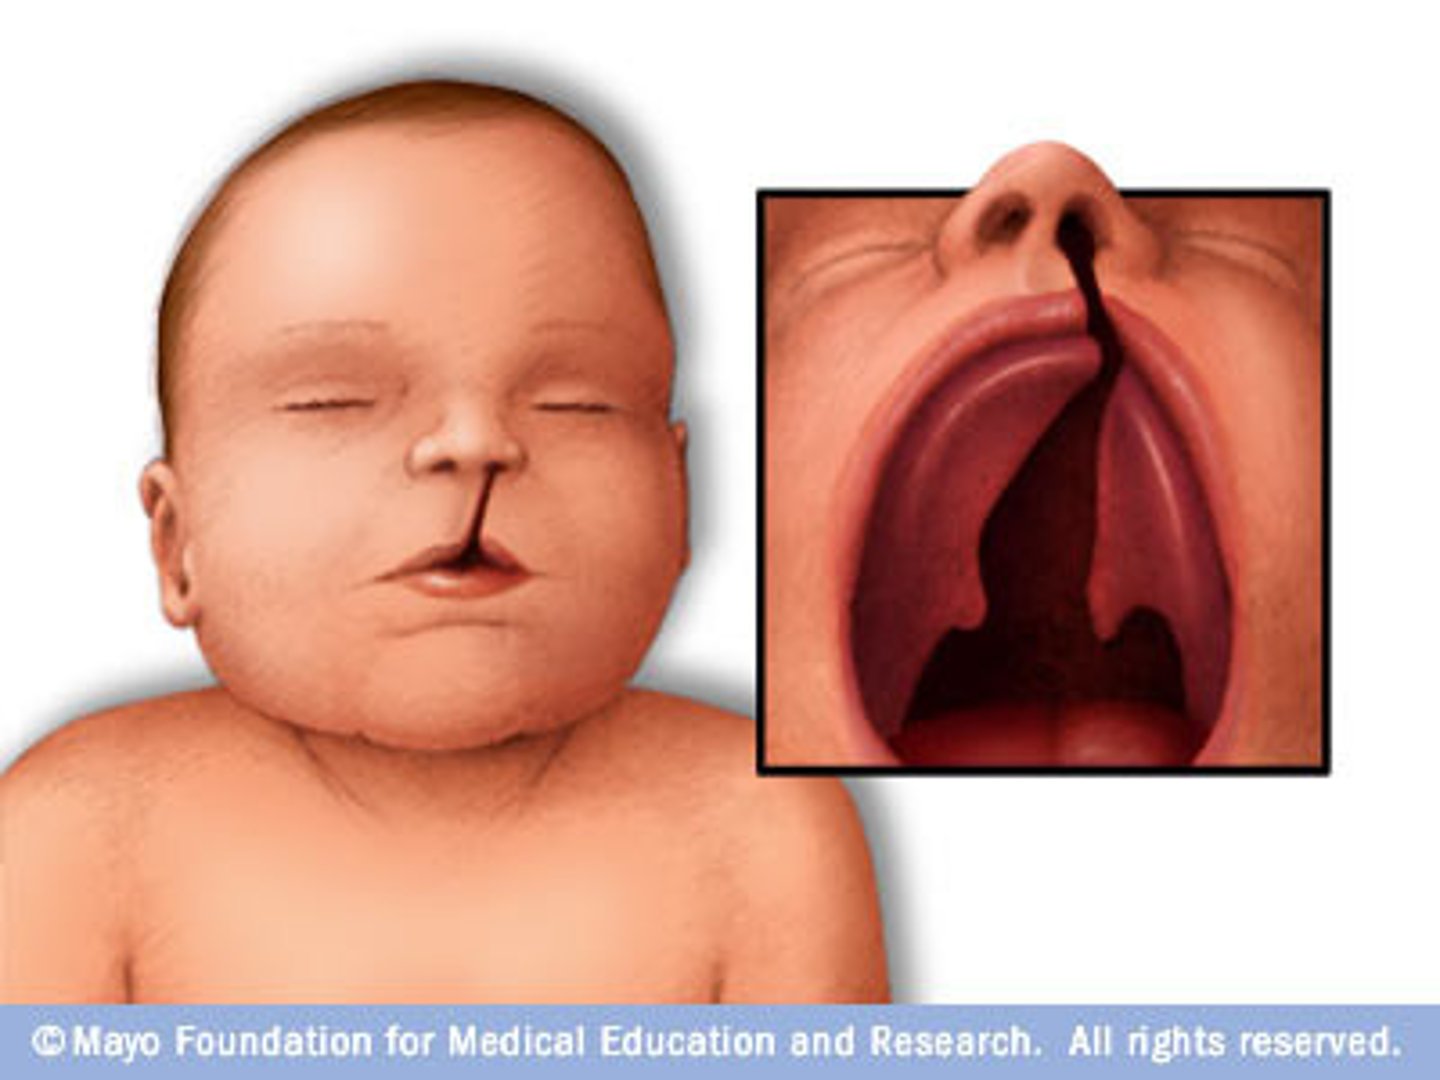

failure of the palatal shelves to fuse result in ____

BIFID UVULA

cleft palate, bifid uvula

patient with cleft palate, mandibular micrognathia, glosspotopis (airway obstruction)

Pierre robin syndrome